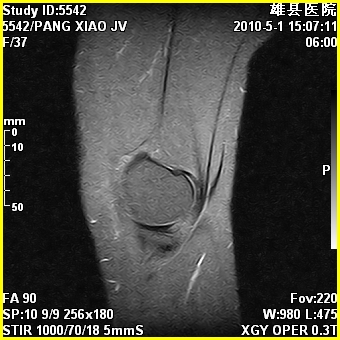

标题: MRI2894:患者右膝关节疼痛两月余,无明显外伤史 [打印本页]

标题: MRI2894:患者右膝关节疼痛两月余,无明显外伤史

右股骨下端前内侧类圆形异常信号,位于干骺端,呈长t1长t2改变,但信号不均,t1图上病灶中心见小片状稍高信号影,t2图上见散在稍低信号影,stir像呈高信号,因病灶较小,缺乏特征性改变,结合患者年龄及部位,考虑嗜酸性肉芽肿可能性大。胫骨关节面下的小囊状异常信号,如果一元论考虑则为嗜酸性肉芽肿,不过发生在这个部位的少见,二元论考虑为邻关节骨囊肿。半月板与前后交叉韧带均未见异常。